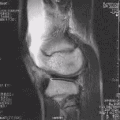

Ressonância magnética (RM) de um joelho. -